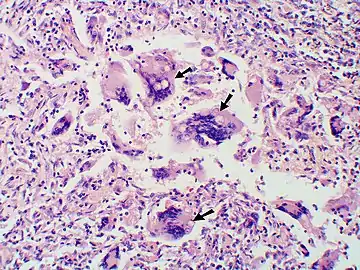

Large, broadly-based budding yeast cells characteristic of Blastomyces dermatitidis in a GMS-stained biopsy section from a human leg.

Inhaled conidia of Blastomyces are phagocytosed by neutrophils and macrophages in alveoli. Some of these escape phagocytosis and transform into yeast phase rapidly. Having thick walls, these are resistant to phagocytosis. Once they have transitioned to the yeast phase, the Blastomyces cells express the protein BAD-1, which helps the yeast cells attach to host cells, and also impairs activation of immune cells while inhibiting release of tumor necrosis factor. [23] In lung tissue, the cells multiply and may also disseminate through blood and lymphatics to other organs, including the skin, bone, genitourinary tract, and brain. The incubation period for pulmonary blastomycosis is 3 to 15 weeks, although 3050% of infections are asymptomatic.[24]

Once suspected, the diagnosis of blastomycosis can usually be confirmed by demonstration of the characteristic broad based budding organisms in sputum or tissues by KOH prep, cytology, or histology.[27] Tissue biopsy of skin or other organs may be required in order to diagnose extra-pulmonary disease. Blastomycosis is histologically associated with granulomatous nodules.